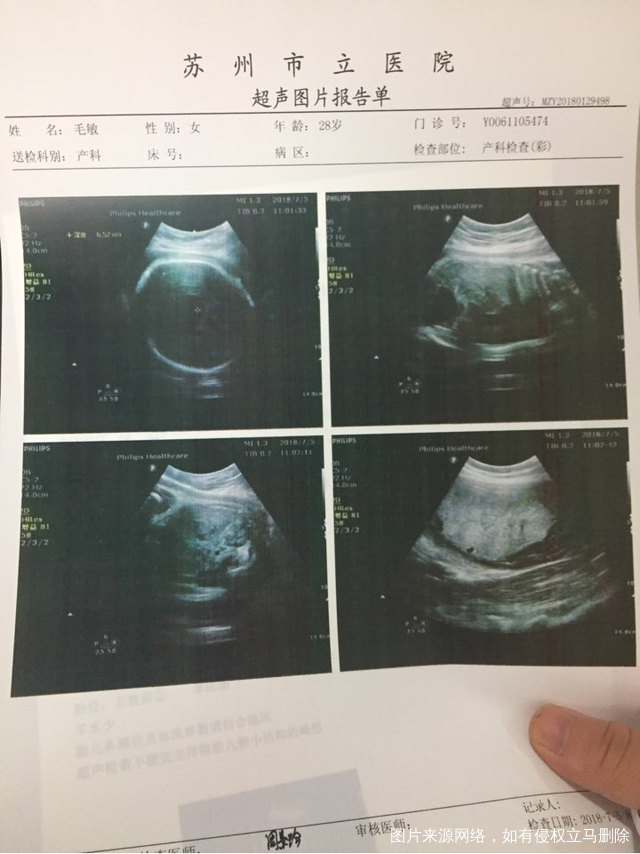

腹直肌分离三公分严重不?